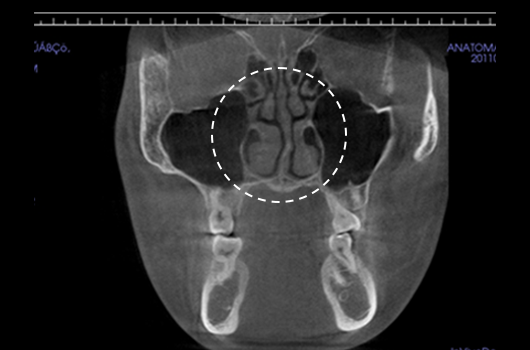

Importance of 3D-CT Scan in Rhinoplasty

During every consultation for rhinoplasty, Braun Plastic Surgery Clinic uses 3D-CT scan to analyze the following issues in three dimensions: A precise surgical plan can be established, and potential side effects reduced by thoroughly understanding the size, shape, and asymmetry of the invisible portions of the nose and the nearby anatomical structures prior to surgery.

3. Analysis of the width and asymmetry of the nasal bone

Analysis of the width and asymmetry of the nasal bone

4. Diagnosis of inferior turbinate asymmetry and surgery for nasal obstruction

Diagnosis of inferior turbinate asymmetry and surgery for nasal obstruction